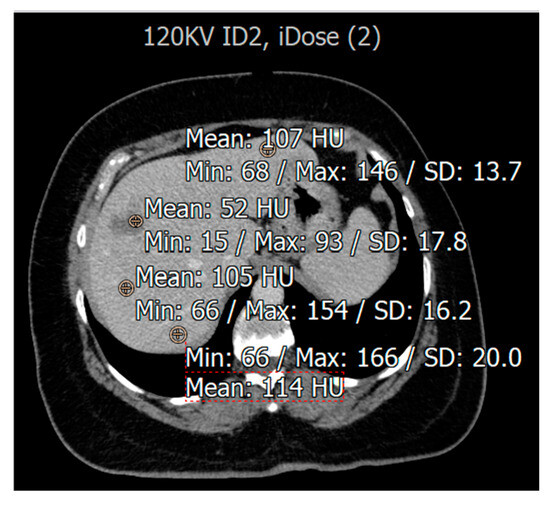

3.2. Evaluation for Patients with Fatty Liver Disease

3.3. Image Quality Evaluation Based on Radiologist